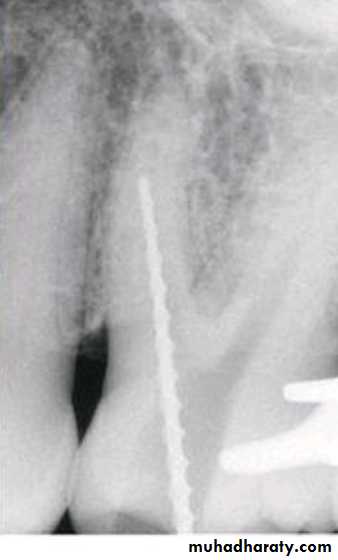

• Instrument breakage

• Canal stripping

• Canal blokage and Loss of working length.

• Ledge formation.• Zipping

• Elbow formation

• Perforation (d & e)

• Canal transportation (e)

• Separated instrument

• Over-instrumentation

Procedural Errors during instrumentation